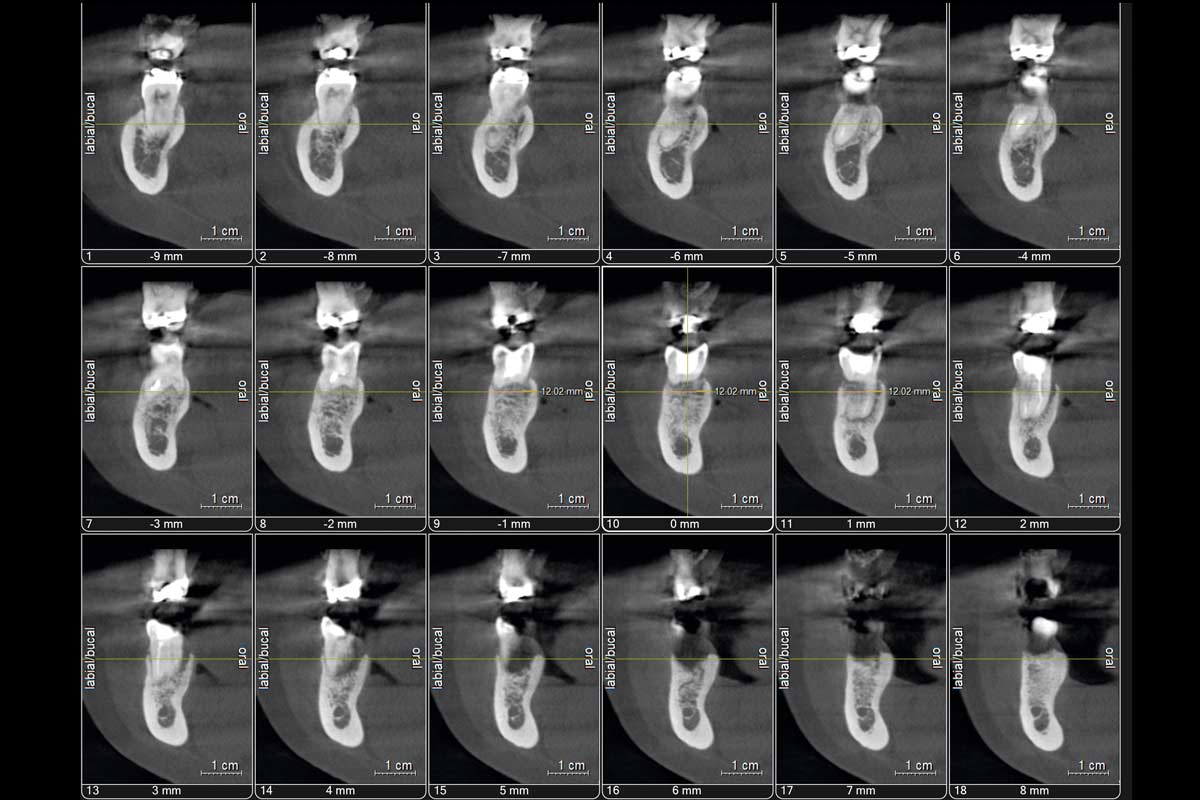

2/19 - CBCT Tooth 4.6

Immediate implant placement using maxresorb® - Dr. Alejandro Signorio